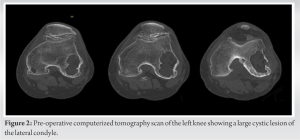

The patient initially presented at age 57 with symptomatic primary osteoarthritis of the left knee for the past 10 + years. He reported pain limiting activity and sleep, lack of full knee extension, and impaired ambulation. Symptoms were refractory to conservative treatments, including weight loss, over-the-counter NSAIDs, corticosteroid injections, a full course of physical therapy, and a prior synovectomy. On examination, body mass index was 31. Left knee alignment was neutral. Range of motion was 5°–120° with no extension lag. The knee was stable to varus/valgus and anterior/posterior stress. Left hip examination was unremarkable. Left knee radiographs showed severe tricompartmental degeneration with tricompartmental osteophytes, joint space narrowing, and multiple intraarticular loose bodies (Fig. 1).

CT showed a large lytic lesion involving most of the lateral femoral condyle, with no aggressive features, most consistent with a benign bone cyst (Fig. 2). After extensive discussion of non-surgical and surgical options, the patient elected to undergo left robotic-assisted TKA, including bone cyst debridement and grafting. The decision to use a cementless knee prosthesis in this case was driven by the patient’s relatively young age, the need to preserve bone stock, and the potential benefits of osteointegration. The possibility of requiring revision TKA implants was discussed.